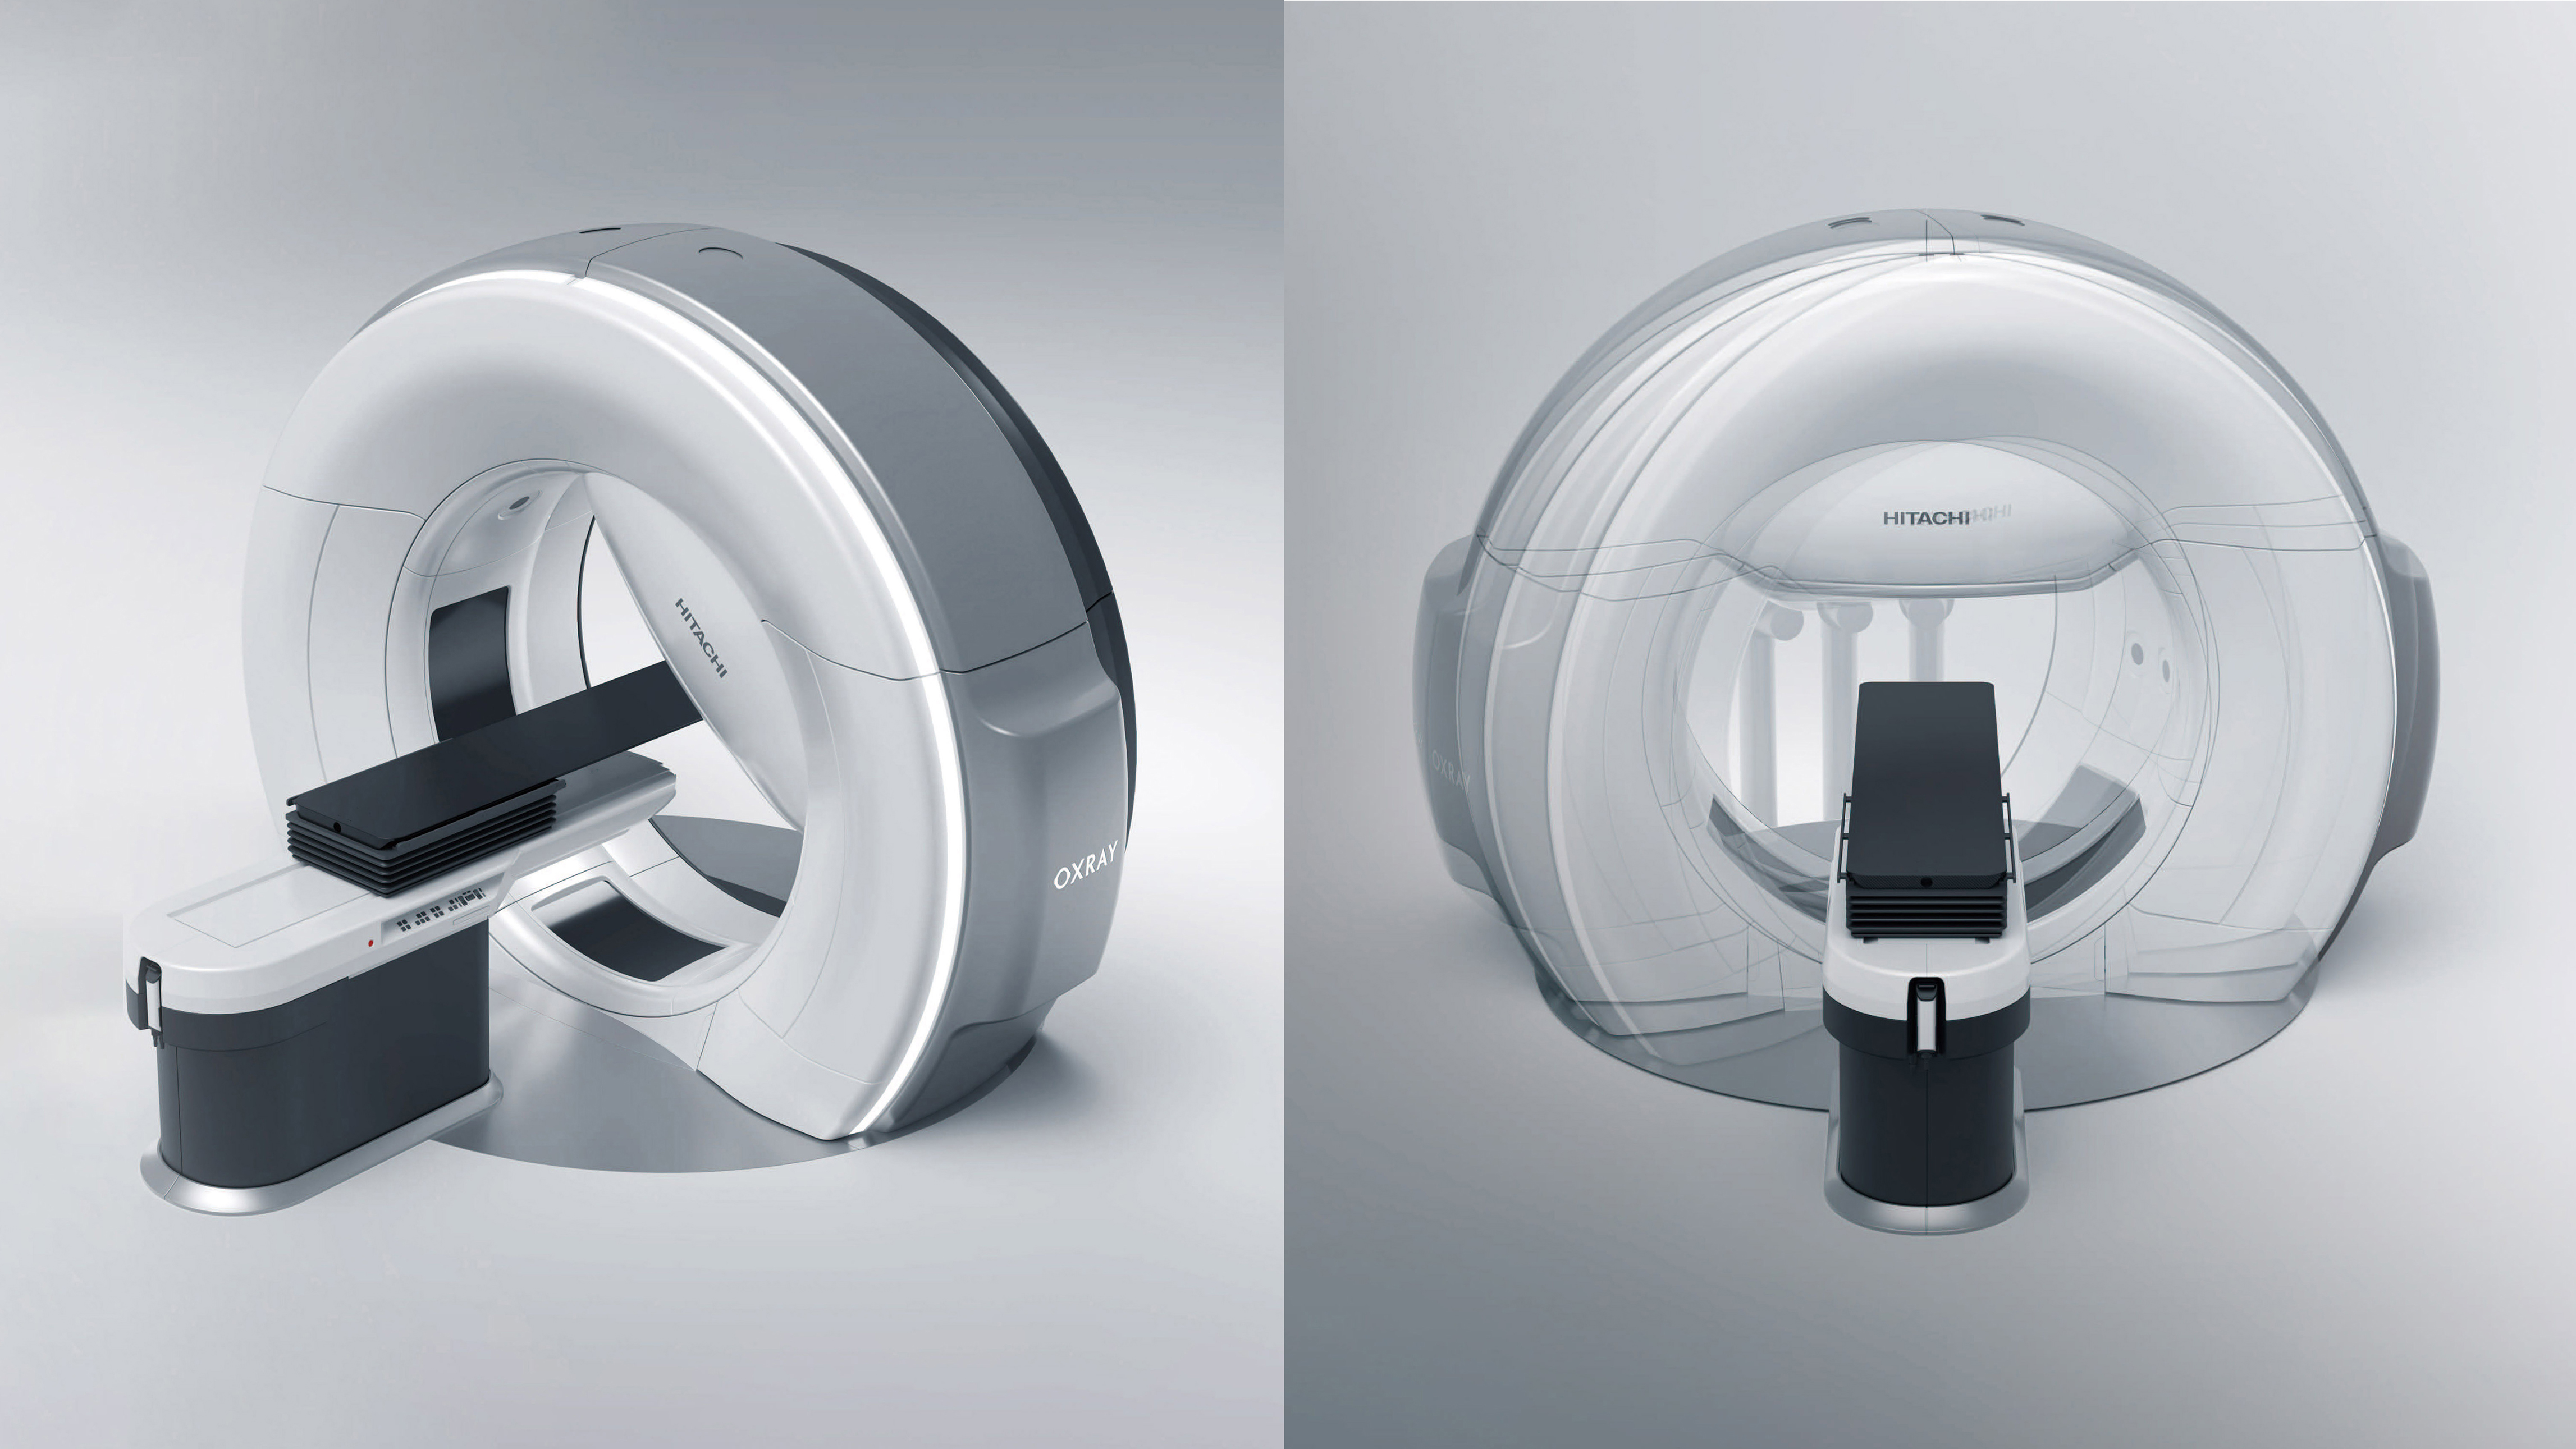

X-ray Treatment device OXRAY

Hitachi High-Tech, Ltd.The OXRAY is a cancer treatment system in which the stage and the inside of the gantry rotate on two axes to deliver X-rays from various angles. The gimbal function enables dynamic tracking of cancer tissue that moves with respiration, which reduces the physical burden and enables high-precision treatment. This reduces side effects and treatment time. In addition, the irradiation range has been expanded to accommodate more cases, and throughput has been significantly improved by integrating individual systems. As of 2025, the system will be available only in Japan.